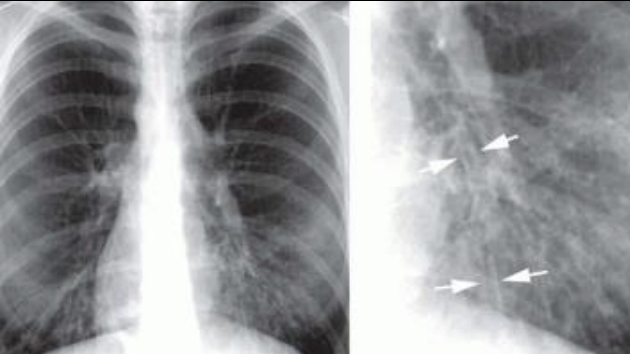

Manguitos peribronquiales: bronquitis crónica

Manguitos peribronquiales

Tranvía